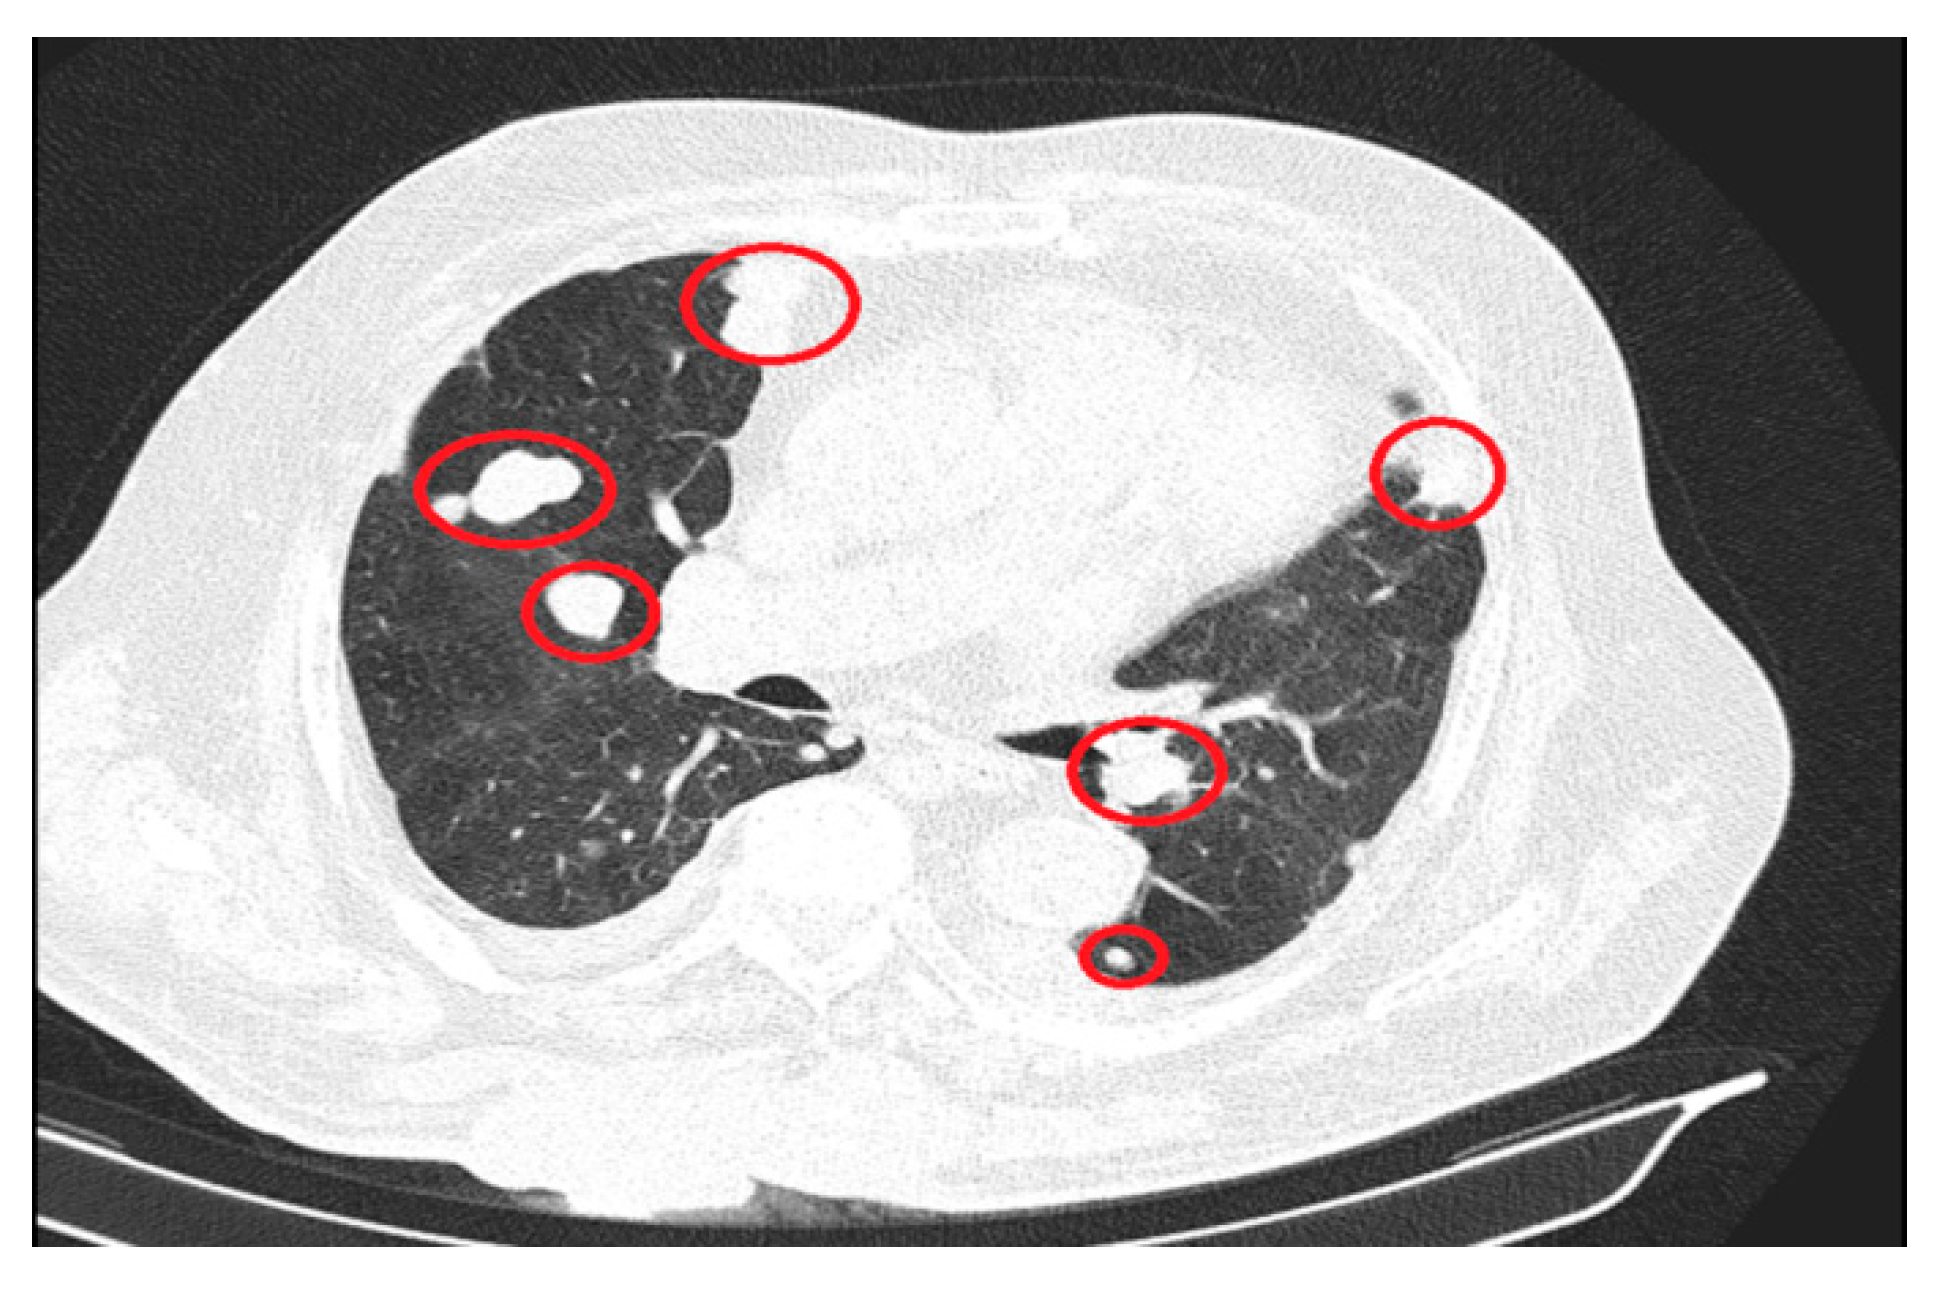

The significant progressions of suggestive lesions for secondary determinations with diffuse distribution in pulmonary parenchyma, pulmonary pleura, and mediastinal pleura were reported, along with the occurrence of pleural fluid in a small quantity bilaterally (Figure 3).

Figure 3. Secondary determinations located in both lung parenchyma.